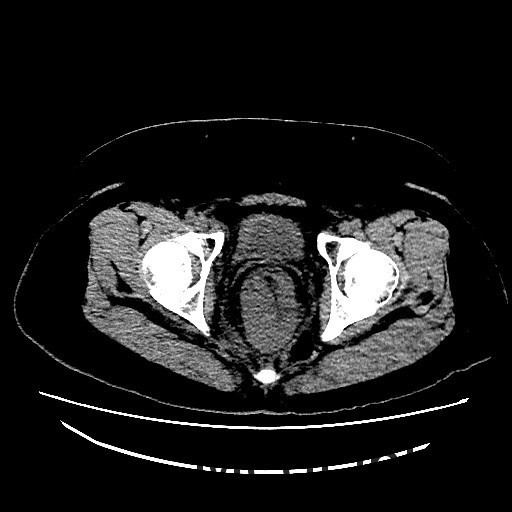

查体:肛查(KC位):肛周未见外痔,直肠指检可及环形多发内痔,部分质地较硬,有触痛,直肠壁可及多发结节,有触痛,指套退出有染血。 辅查:腹部CT示:直肠癌,累及肠壁全层,并周围肠系膜多发淋巴结转移,全身核素骨扫描结果提示:右侧坐骨轻度代谢活跃,建议定期复查以排除骨转移瘤可能,肿瘤标记物未见明显异常。肠镜示:1.直肠Ca?2.结肠息肉(已钳除)。

讨论:胃肠道是原发性结外淋巴瘤最常见的累及部位。其中胃是最常见的发病部位,其次是小肠,而结肠和直肠少见。本例属于直肠淋巴瘤,属于少见肿瘤,影像表现与直肠癌相似,因此临床常常误诊为直肠癌,本例即误诊为直肠癌。影像学上只要认真观察一般能通过以下几点将两者鉴别开:淋巴瘤一般累及的肠段较长,肠壁较厚,肠腔变窄不明显,呈动脉瘤样扩张,没有肠梗阻表现,周围脂肪界面清晰。而大肠癌则相对较局限,常伴有肠腔的狭窄及肠梗阻的表现,而且常通过浆膜直接向周围浸润,周围脂肪间隙模糊。只要认真寻找这些影像征象,还是能够将两者较好的区别开来。